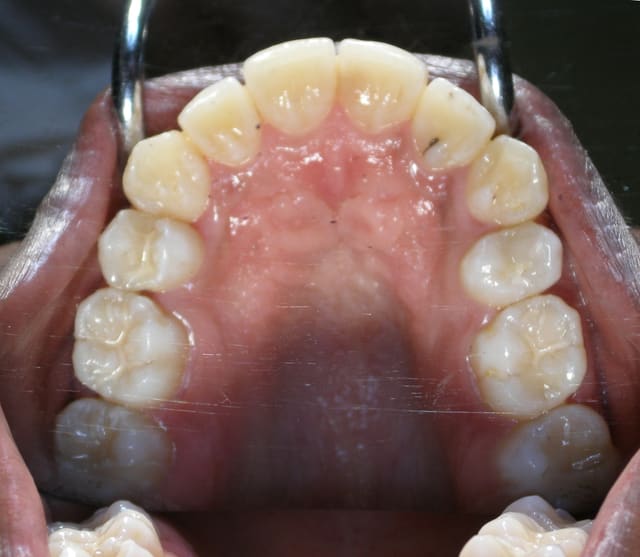

jeune fille pour une désinclusion de 23, 10 ans sur la carte vitale, dentition en avance pour son age

sur la pano j'étais parti pour 2 surnuméraires

sur la photo 2 on distingue les 2 germes l'un au dessus de l'autre (eh non pxav je n'y arrive tjrs pas pour les photos)